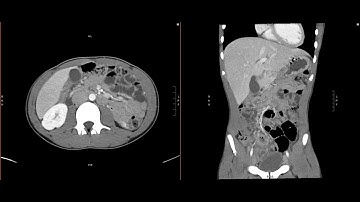

Abdominal Imaging Call Prep Cases: Acute Uncomplicated Appendicitis (CT) Search Pattern